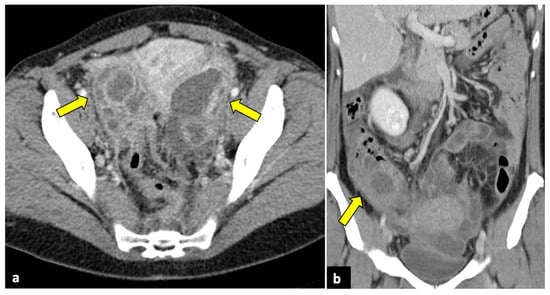

Pelvic malignancies, most commonly ovarian, cervical, and endometrial uterine cancers, can induce pain of different intensities and durations. Gynaecological cancer may present with sudden onset in cases of advanced stages, with the invasion of adjacent structures that lead to several complications, such as intestinal perforation, thrombosis, and intestinal or ureteral obstruction (Figure 10) [71,72,73].

Figure 10.

Advanced uterine cervical cancer in a 58-year-old subject attending the emergency department for abdominal pain and haematuria. CT axial (a), sagittal (b), and coronal (c) non-contrast images reveal the presence of a pelvic mass (blue arrows) and ureter causing ureteral obstruction (yellow arrows). The patient further underwent an MRI examination (d–f), which demonstrated a cervical tumour (blue arrows) invading the parametrium and ureters bilaterally (yellow arrows), the vagina, and the bladder. The uterine cavity was also obstructed and dilatated (red arrows).